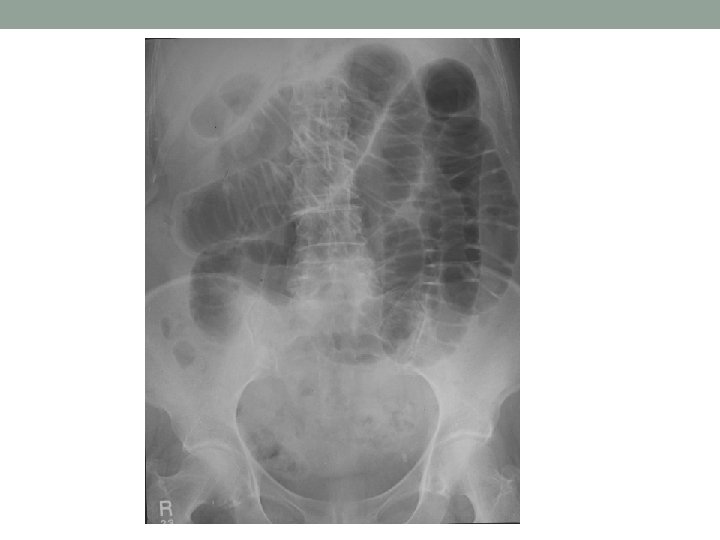

AXR Demographics/ Type of XR Black: dilated loops / Air • Small = central, valvulae conniventes • Large = Peripheral, Haustrae White: Calcification • Renal stones/ Gallstones • Foreign Bodies • Bone Grey: soft tissue • • Liver, spleen, pancreas, gall bladder, ovary, uterus Enlargement, calcification Abdominal wall muscles, hernias Stool Re-review and summarise

Air in Abdomen • Post-op/ Post-ERCP • Perforation • Cholangitis • Abscess • Gallstone Ileus